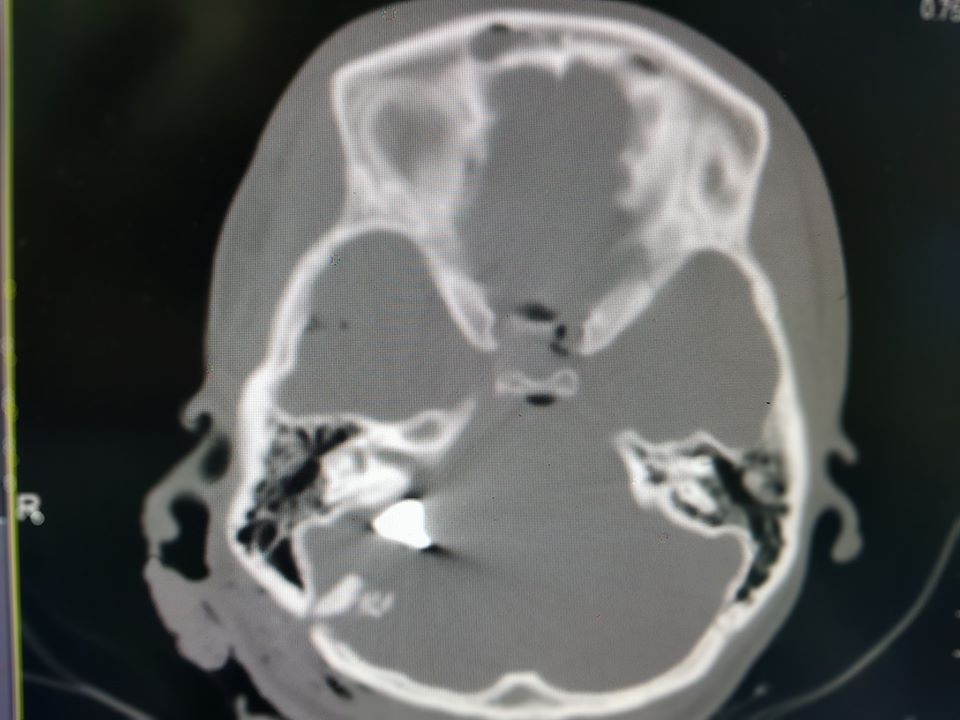

"Крайне тяжелое состояние, кома III степени, искусственная вентиляция легких и сверхвысокие дозы препаратов, поддерживающих артериальное давление. Взрывная черепно-мозговая травма, перелом костей свода и основания черепа, металлические обломки повредили жизненно важные участки мозга. Травма, не совместима с жизнью", - написал Толубаев.

последствия взрыва петард на балконе многоэтакжкиостатки взорвавшихся петард на балконе многоэтажкирентгеновский снимок черепа раненой в голову девушкискриншот страницы в соцсети врача больницы